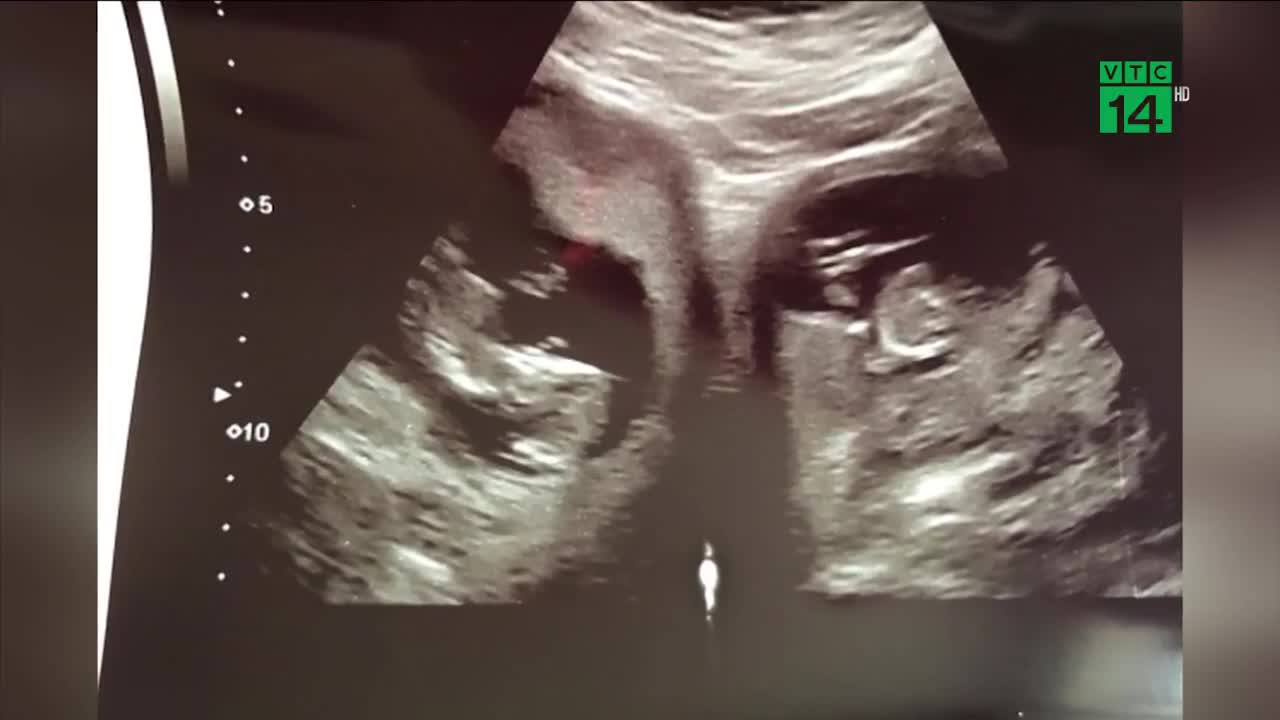

Cặp song sinh nằm ở 2 tử cung: 500 triệu ca mới có 1

Một bà mẹ ở Anh mang song thai, đặc biệt người mẹ này có tới tận 2 tử cung, và mỗi em bé lại nằm ở một tử cung độc lập.